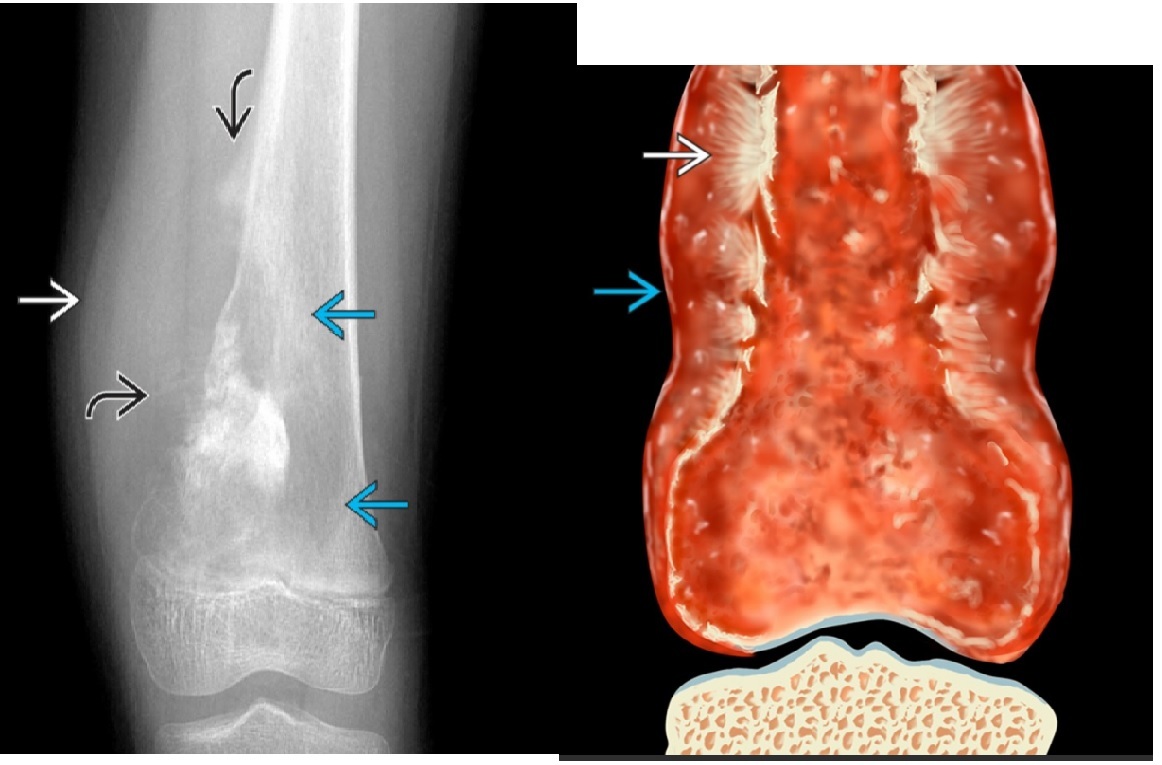

osteosarcoma

Femur (40%) and proximal tibia commonest sites (15%)

**Aggressive periosteal reaction **

- Sunburst

- Codman triangle

- Lamellated (onion skin)

**High grade = Met to the lung

**

Reverse zoning phenomenon - dense mature matrix in the centre, less peripherally

DDx

ewings Sarcoma